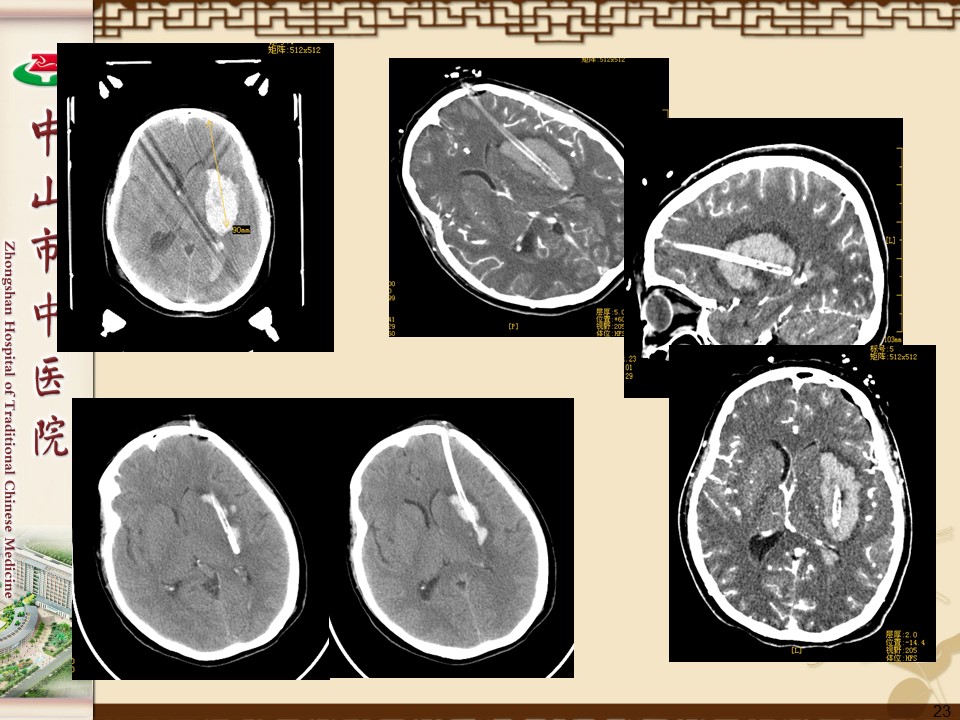

脑出血的外科治疗PPT

高血压脑出血80%在幕上,20%在幕下。常见的出血部位是:

1、壳核出血,约占60%(44%~69%);

2、丘脑出血,约占10%(10%~13%);

3、大脑半球白质出血,约占10%(10%~          26%);

4、脑干出血,约占10%(6%~17%);5、小脑出血,约占10%(4%~13%)。